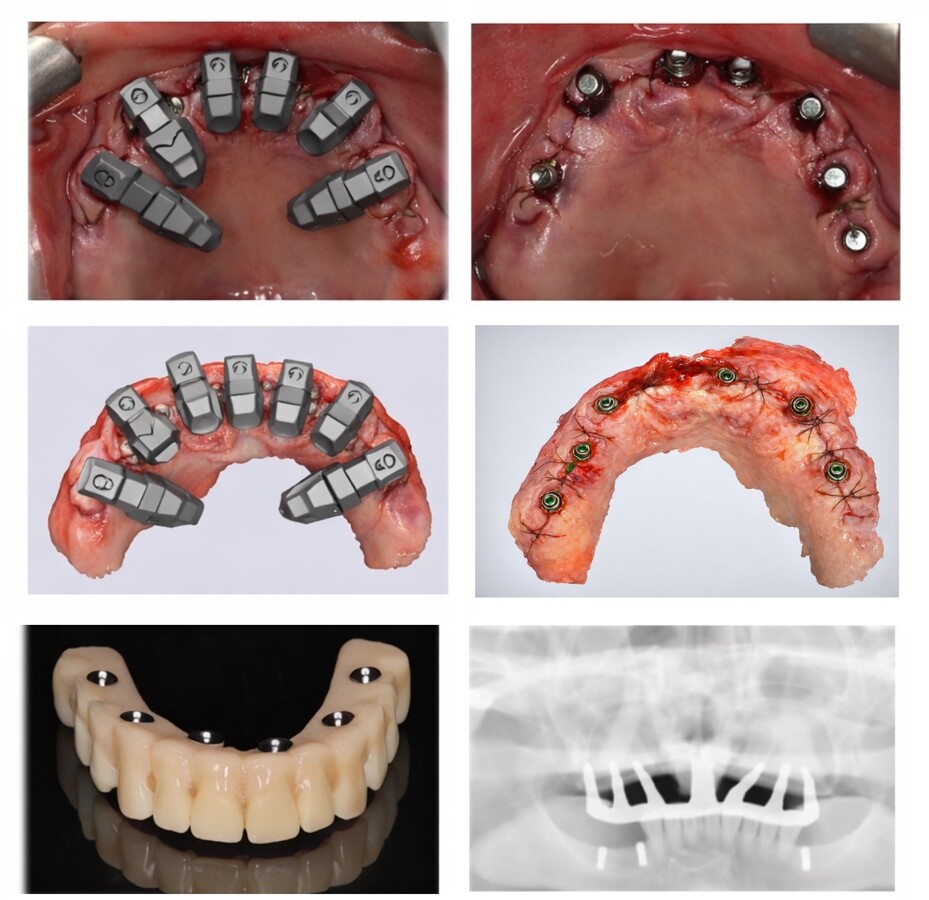

Figura 5. Secuencia del sistema DirectIP en la realidad clínica (arriba) y en la realidad virtual (centro). En las imágenes inferiores, la prótesis y la radiografía de control, donde se observa la pasividad lograda en un caso de arcada completa.